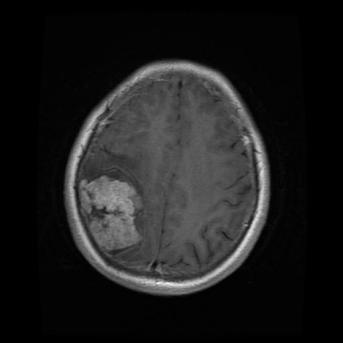

Figure 3. The Image Generated by DCGAN (Left one is no tumor).

In the image above, the right one is the image with meningioma generated by the DCGAN. We can see that there is a tumor at the upper left, which is kind of brighter. However, the complexity of the brain makes it hard for the model to learn and generate images very well. In this case, it’s not easy for the DCGAN to generate really similar images. Just like Figure 3, It rarely has the the detail for the brain compared with the original image, especially the image with meningioma. In the image with meningioma, it’s hard to find any texture or organ that should be contained in the brain. However, the CNN model may still learn from the images generated by the DCGAN by capturing specific features like lighter areas, and the CNN model has increased its accuracy.